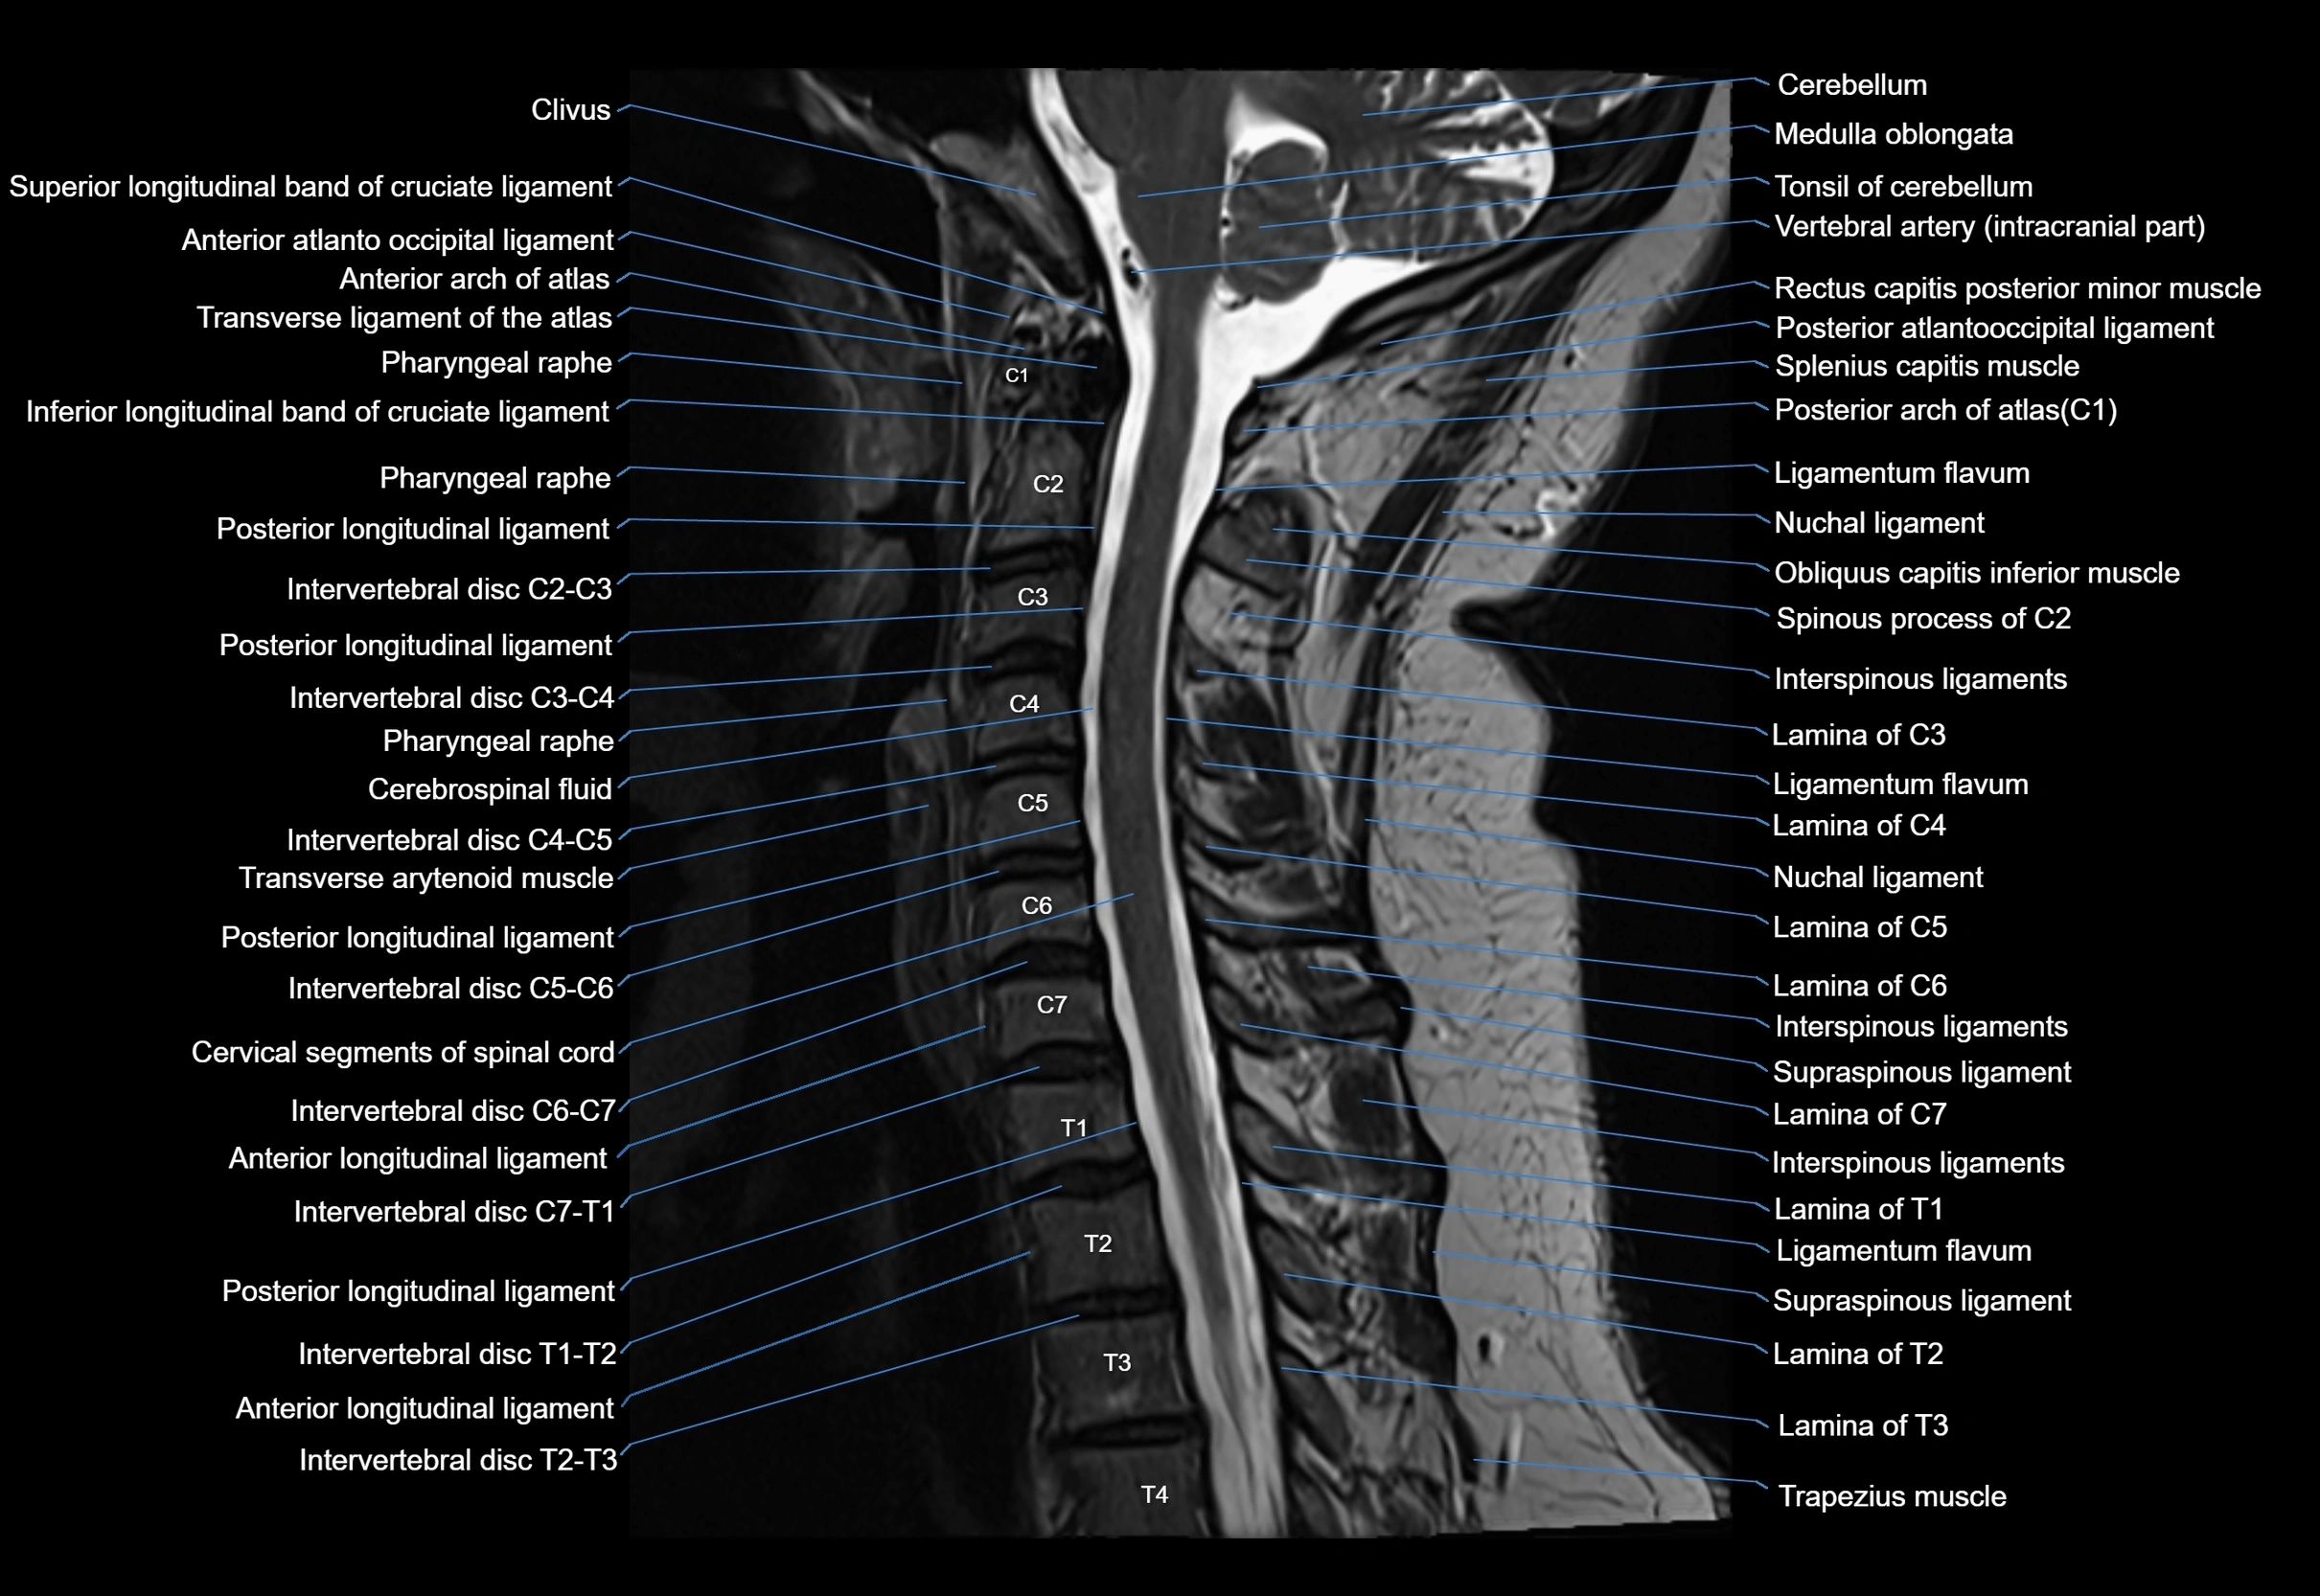

MRI appearance

T1-weighted images:

• Annular epiphysis: Low signal cortical rim at the vertebral margin

• Adjacent marrow: Intermediate-to-high signal in the vertebral body

• Disc interface: Clear delineation between bone and annulus

T2-weighted images:

• Annular epiphysis: Low signal intensity line

• Endplate cartilage (in younger patients): Intermediate signal

• Intervertebral disc: High signal nucleus pulposus

STIR:

• Annular epiphysis: Low signal cortical rim

• Adjacent marrow: Suppressed fat signal with preserved bony outline

• Utility: Highlights marrow and endplate interface in developing spine

MRI image

image